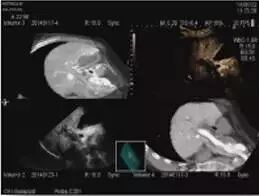

多影像融合介入导航系统(Real-time Virtual Sonography )

RVS(Real-time Virtual Sonography )是世界首创技术,由于采用了高精度的磁定位系统,操作者随意移动探头更换切面时,CT/MR/US造影的图像都会实时与之联动。这一技术使超声引导下的 RFA 治疗技术得到巨大的提高,病灶显示更准确,诊断更充分,治疗更安全,操作更简便。